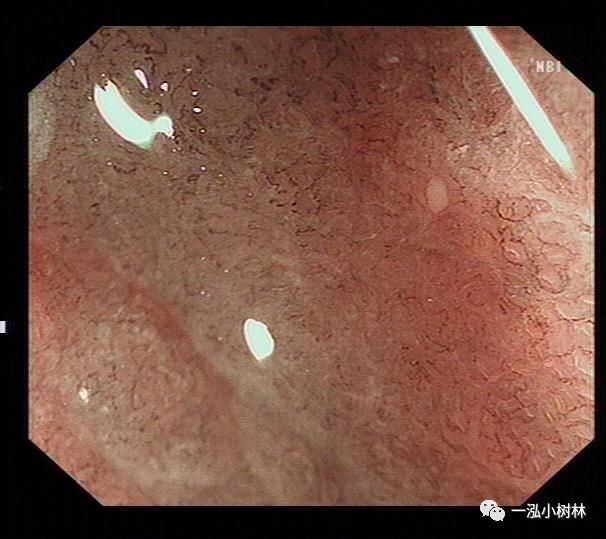

NBI+ME内镜表现:萎缩区域NBI放大可见胃小凹消失或不清晰,树枝状血管显露,黏膜苍白及萎缩边界更明显,多以幽门胃窦部为中心,随着萎缩的加重,胃体黏膜也散见,肠化区域可见胃小凹呈绒毛状,可见到“亮蓝嵴”“白色不透明物质”征。

例4

女性,42岁,萎缩性胃炎+肠化+Hp感染

亮蓝嵴(LBC):位于上皮细胞表面呈脑回样结构脊部的纤细、蓝白色的腺样结构。特征:NBI才能观察到。NBI显示亮蓝色细线样反光,位于上皮细胞边缘。提示肠上皮化生刷状缘。是内镜诊断胃黏膜肠上皮化生的有效标志。